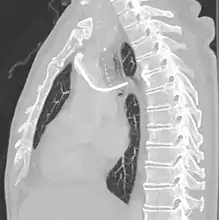

Рентгеноскопія корисна для проведення імплантації портів.[1]

Повторна рентгенограма органів грудної клітки може негайно виявити ускладнення, пов'язані з процедурою. Це можуть бути пневмоторакс, гемоторакс або неправильне положення катетера.

Порти можуть бути введені у верхню частину грудей або руку. Точне позиціонування саме по собі є змінним, оскільки його можна встановити, щоб уникнути видимости при носінні сорочок із низьким вирізом, чи щоб запобігти надмірному контакту з рюкзаком або ремінцем бюстгальтера. Найбільш поширене розміщення — у верхній правій частині грудної клітки, при цьому сам катетер проходить через праву яремну вену і вниз до серця пацієнта.